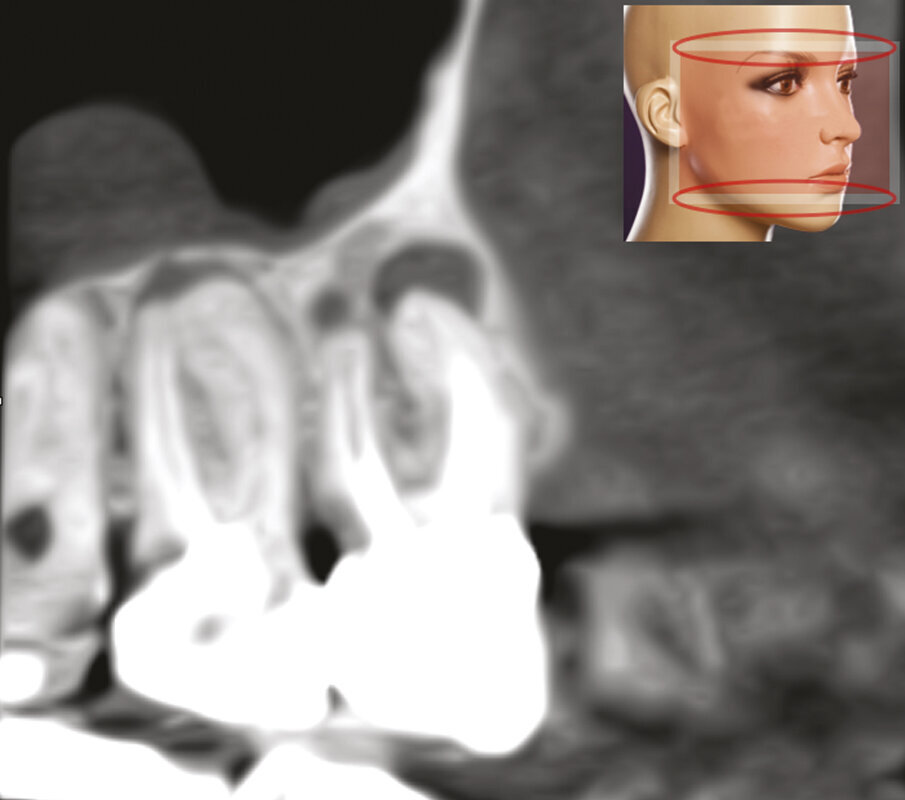

Fig. 2c - La CBCT mostra l’inclinazione distale della radice distovestibolare del primo molare.

Fig. 2d - La sezione coronale mette in evidenza il fatto che la radice distovestibolare del primo molare è vestibolare alla radice mesiovestibolare del secondo molare.

Fig. 2e - Le quattro sezioni assiali mostrano come la radice distovestibolare del primo molare sia vestibolare rispetto alla radice mesiovestibolare del secondo molare. Questa particolare situazione anatomica rappresenta una ovvia controindicazione all’approccio chirurgico.

Figg. 4a-4c - - La CBCT offre la possibilità di fornire e immagazzinare immagini radiografiche leggibili su vari piani sia orizzontali che verticali: assiale, sagittale e coronale.